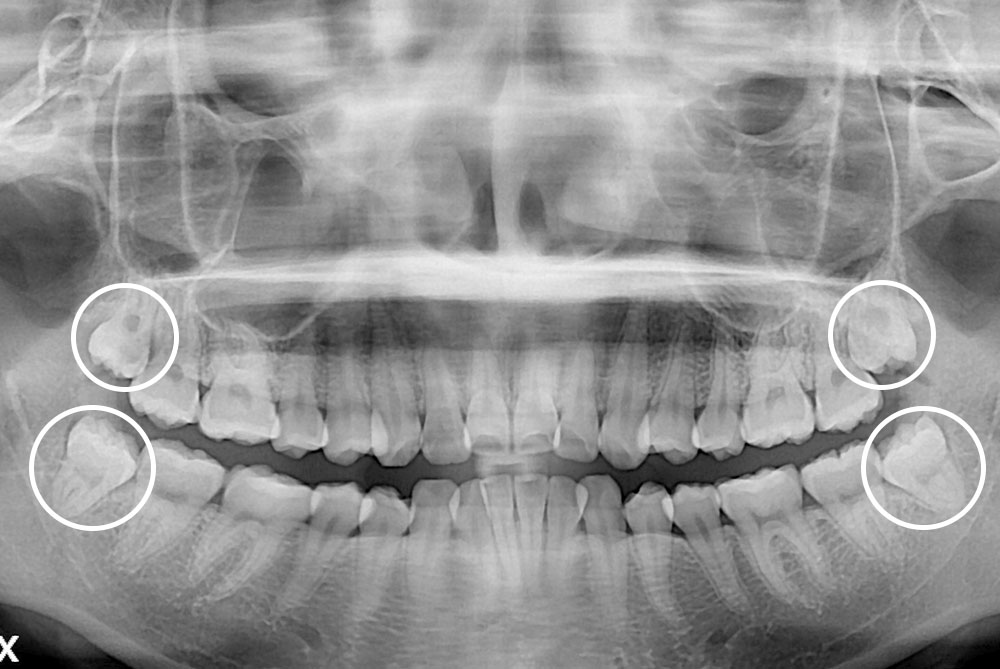

[사랑니] 매복 사랑니 발치

치료전 : 2019-05-14